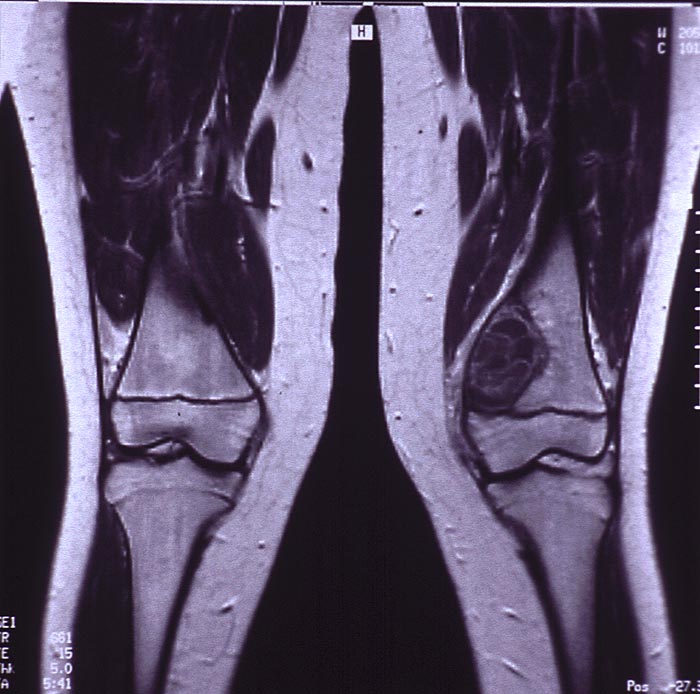

PathoPic – image database / PathoPic ID 5036 - Aneurysmatische Knochenzyste

Aneurysmatische Knochenzyste

MRT: Radiologisch erkennt man in der distalen linken Femurmetaphyse medial eine exzentrisch gelegene mehrkammrige Osteolysezone proximal der offenen Epiphysenfuge.